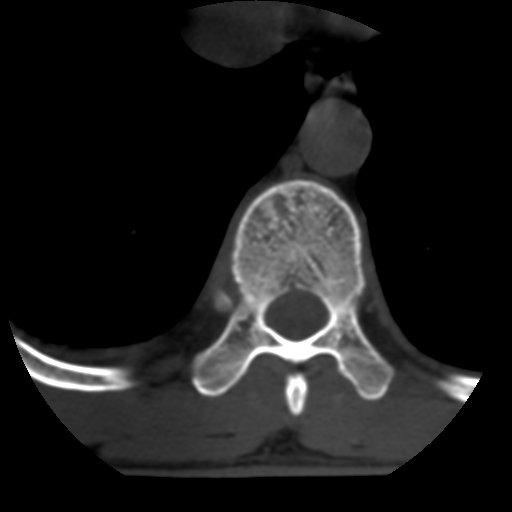

男,31岁,从6米高处坠落伤两天,腰背部疼痛,临床要求ct扫描胸10-腰1。请大家帮忙看看骨质有问题吗?

t12、l1锥体前缘轻度楔形变,平扫示椎体前缘骨小梁欠规整,第9幅图示椎体前缘骨质不连续,结合外伤史考虑椎体轻度压缩骨折。

楼主扫描层厚可能较大,每个椎体只有三个层面.

从所示层面分析,无明确骨折征象,象类似病人我个人会建议mri除外骨挫伤.

从上查骨窗第九片椎体前缘皮质显示断裂.压缩骨折?